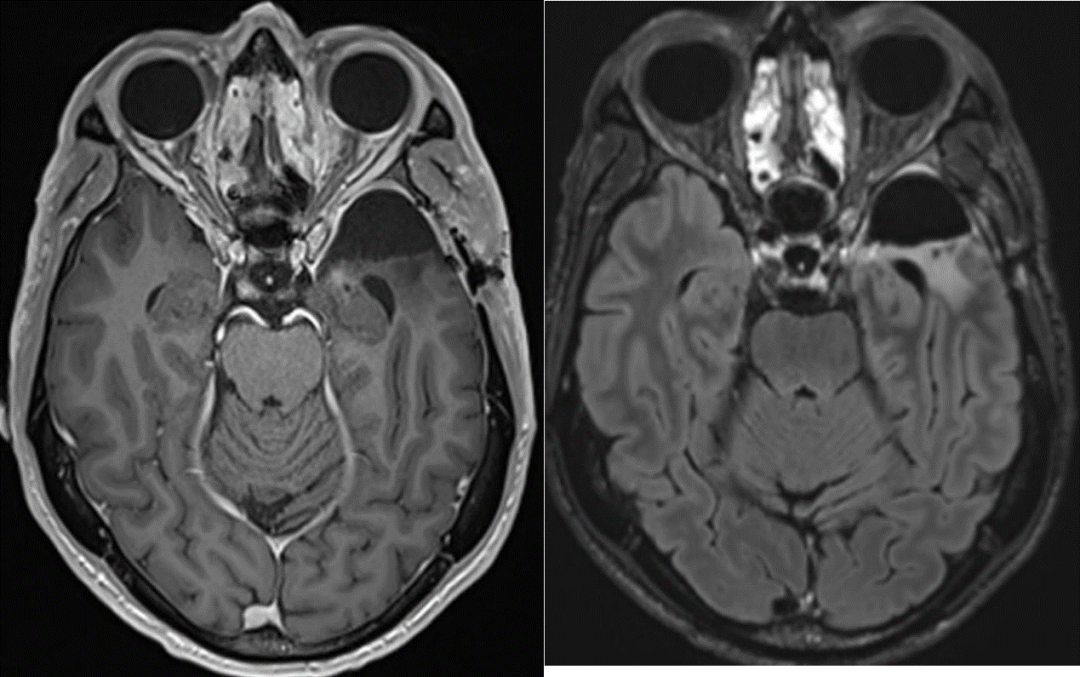

當地時間2024年5月14日,理查德通過社交媒體宣佈,治療近1年後,自己病情穩定、未檢出GBM復發跡象。他表示,自己留取了寶貴的生物樣本,包括新輔助治療前後的腦腫瘤樣本,整個治療過程中的血、糞樣本,以及腦脊液樣本等,未來會進行更詳細的轉化研究。

2024年3月19日,理查德·斯科萊爾在個人社交媒體發佈了治療10個月後的腦部複查結果。/Richard Scolyer